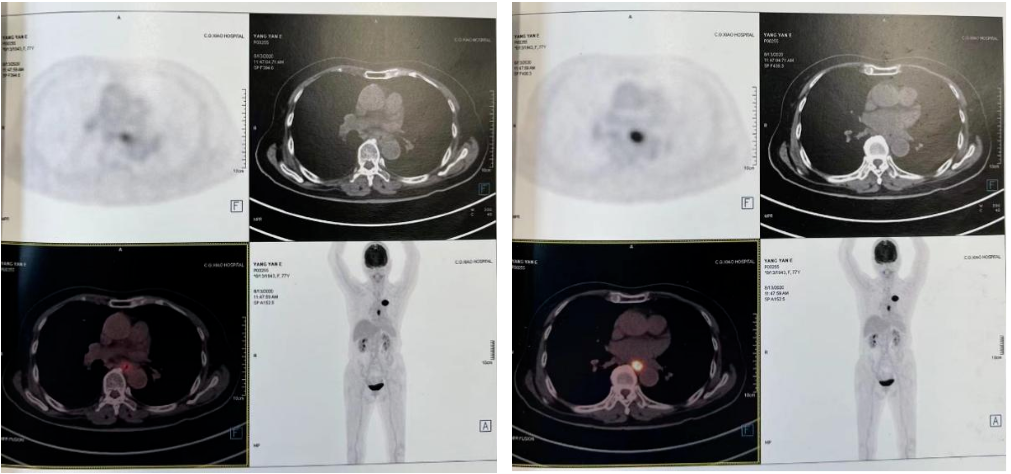

2021-10-28外院PET-CT:原食管胸下段管壁高代谢灶较前缩小,放射性较前减低,现大小约15×17×17mm,SUVmax 3.1,考虑为治疗后改变。左肺上叶团块状高代谢灶较前缩小,放射性摄取较前减低,现大小约25×18mm,SUVmax 2.1,考虑为治疗后改变。

2022-03-28 PET-CT:1、食管癌放化疗后,食管胸中段管壁不规则增厚伴结节状代谢增高,与上次(2021-10-28)PET/CT检查对比,病灶代谢较前明显增高,考虑为肿瘤复发病灶。2、左肺癌放疗后及靶向药治疗后,原左肺上叶团块状高代谢“肿瘤灶”,现范围较前稍缩小,代谢较前稍减低,考虑为治疗后改变(肿瘤完全活性受抑,伴少许炎性反应可能)。

2、左肺腺癌cT3N0M0IIb期综合治疗后

二线治疗

2022年-04-01~2022年08-行化疗+靶向+免疫治疗,具体方案为白蛋白紫杉醇260mg/m2即400mg d1 q3wX6周期;化疗同时行尼妥珠单抗400mg q3w;化疗同期行斯鲁利单抗200mg q3w治疗及维持治疗至今。